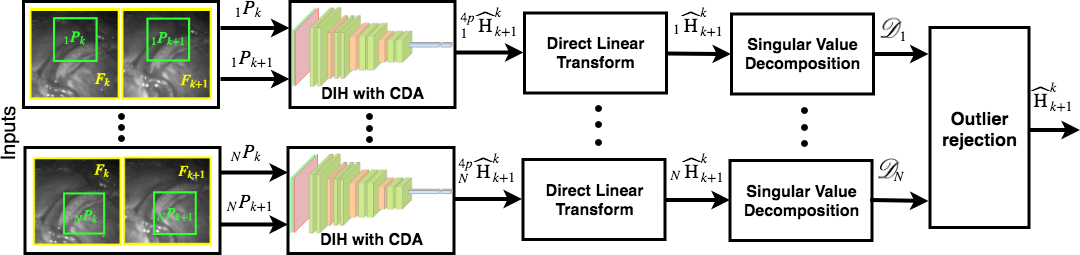

Mosaic from an image sequence can be generated by finding the pairwise homographies between adjacent frames, followed by computing the relative homographies with respect to a reference frame. The GT pairwise homographies are unknown in fetoscopic videos since they are captured from a monocular camera. Therefore, only through visualization, we can observe the error accumulated over time. For minimizing this error, in our proposed DSM, the relative homography is learned between patches that are extracted from a single image following the CDA (Sec. 3.1). Unlike [4], in practice homography is computed between two adjacent frames, having specular highlights and lack of texture, in fetoscopic videos. Therefore, testing by using pairs of patches from two adjacent frames results in varying . To overcome this error, we propose an outlier rejection step (Sec. 3.2) to improve the estimation. During testing (Fig. 2), we compute homographies between pairs of adjacent frames times by randomly selecting the location of PA. The estimated is converted to by applying Direct Linear Transform (DLT), followed by its decomposition using Singular Value Decomposition (SVD) and outlier rejection for removing inaccurate estimations.

3.2 Homography Matrix Decomposition and Outlier Rejection

and , are the translation components. By solving eq. 3, we obtain the decomposed parameters, [7]. Next, for Fk and Fk+1, we compute for iterations by selecting a new random patch pair nPk and nPk+1 at each iteration and obtain decompose parameters, represented for example as . The variations in and are very small due to fixed scale assumption, but are significant in and . Since the first and third matrices in eq. 3 are orthogonal, , filtering either of the two has the same effect. We apply median filtering, since it is useful for mitigating the effect of the outliers, to to get its argument , giving the most consistent value for . This argument is used to obtain , , , and , that are then plugged into eq. 3 to get the consistent .